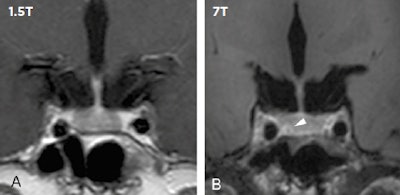

In clinical imaging, 7-tesla MRI can make a difference in detecting and ruling out pituitary lesions. Compared with low-field MRI, 7-tesla MRI in 16 patients resulted in three newly detected pituitary lesions (shown by the white arrow), which had direct implications for neurosurgical planning (see de Rotte, Groenewegen A, Rutgers DR et al, European Radiology, January 2016, Vol. 26:1, pp. 271-277). All images courtesy of Dr. Jeroen Hendrikse.Nevertheless, it's an exciting time for 7-tesla application, with potential for its use in the assessment of the total burden of disease and in clinical neurodegenerative disease research, allowing the quantification of flow in the small perforating arteries, which is crucial in the development of small vessel disease, such as white-matter lesions of presumed vascular origin.